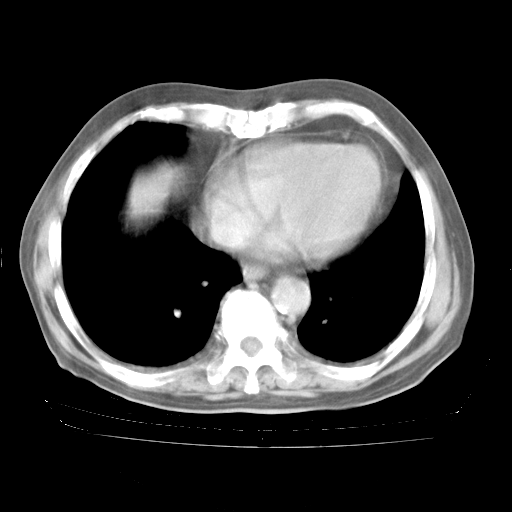

4月28日肺部CT——再次出现类似去年5月9日——透光度降低,“间质性”改变。

4月28日肺部CT——再次出现类似去年5月9日——磨玻璃样、间有“粟粒样”改变。

4月28日肺部CT